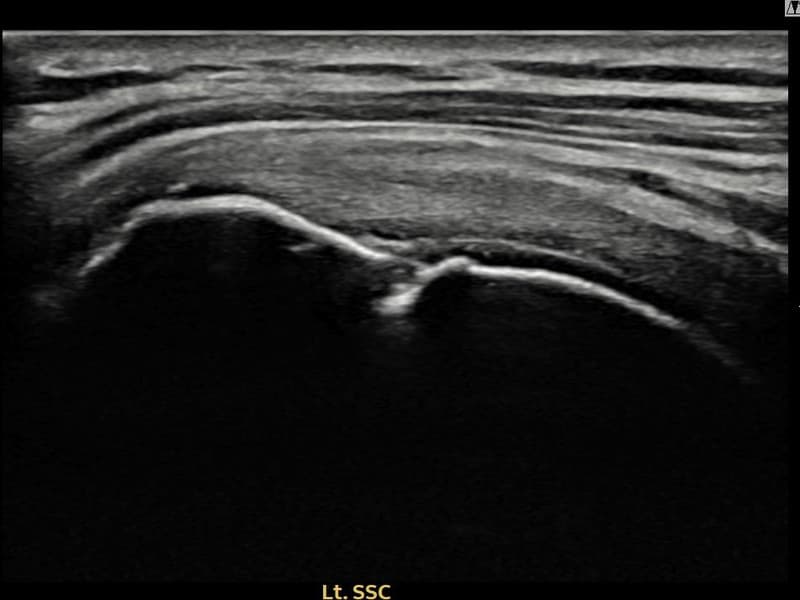

시술 전 초음파 측정 결과 파열 크기는 11mm × 4mm (힘줄 두께의 약 44% 결손)로 확인되었습니다. 시술 전 초음파에서 좌측 극상근건 부착부의 에코 단절과 힘줄 내 결손 소견이 확인되었습니다. 시술 후 초음파에서 부착부 연속성이 회복되고 결손 부위가 재생 조직으로 채워진 것이 관찰되었습니다.

50대 후반 남성 환자분으로, 건설 현장 관리직으로 근무하시며 팔을 자주 들어 올리는 작업을 반복해 오신 분이었습니다. 처음엔 야간에만 통증이 있었으나 점차 팔을 앞으로 올리는 동작 자체가 힘들어져 내원하셨습니다. 초음파 검사에서 좌측 극상근건 부착부의 부분파열이 확인되었으며, 수술 없이 초음파 유도 하 축소봉합술로 치료 가능하다고 판단하였습니다. 시술은 30분 이내에 완료되었고 당일 귀가하셨으며, 이후 단계적으로 재활 운동을 시행하였습니다. 시술 10주 후 추적 초음파에서 극상근건 부착부 연속성이 완전히 회복된 것이 확인되었고, 통증 없이 현장 복귀에 성공하셨습니다.